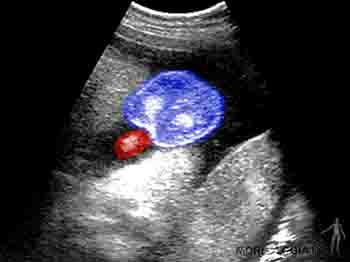

En el quinto mes, los miembros inferiores crecen y adquieren una proporción más armónica. A esta edad la madre percibe los movimientos fetales y es posible auscultar los latidos fetales. La piel está cubierta por una secreción grasosa llamada unto sebáceo o vérnix caseosa. Esta capa grasosa evita la maceración de la piel del feto que flota en el líquido amniótico. En este período se canalizan los canales anal y vaginal, y comienza la migración del testículo. Ecográficamente ya son visibles los riñones y la vejiga urinaria (Figuras 2-21a y b).